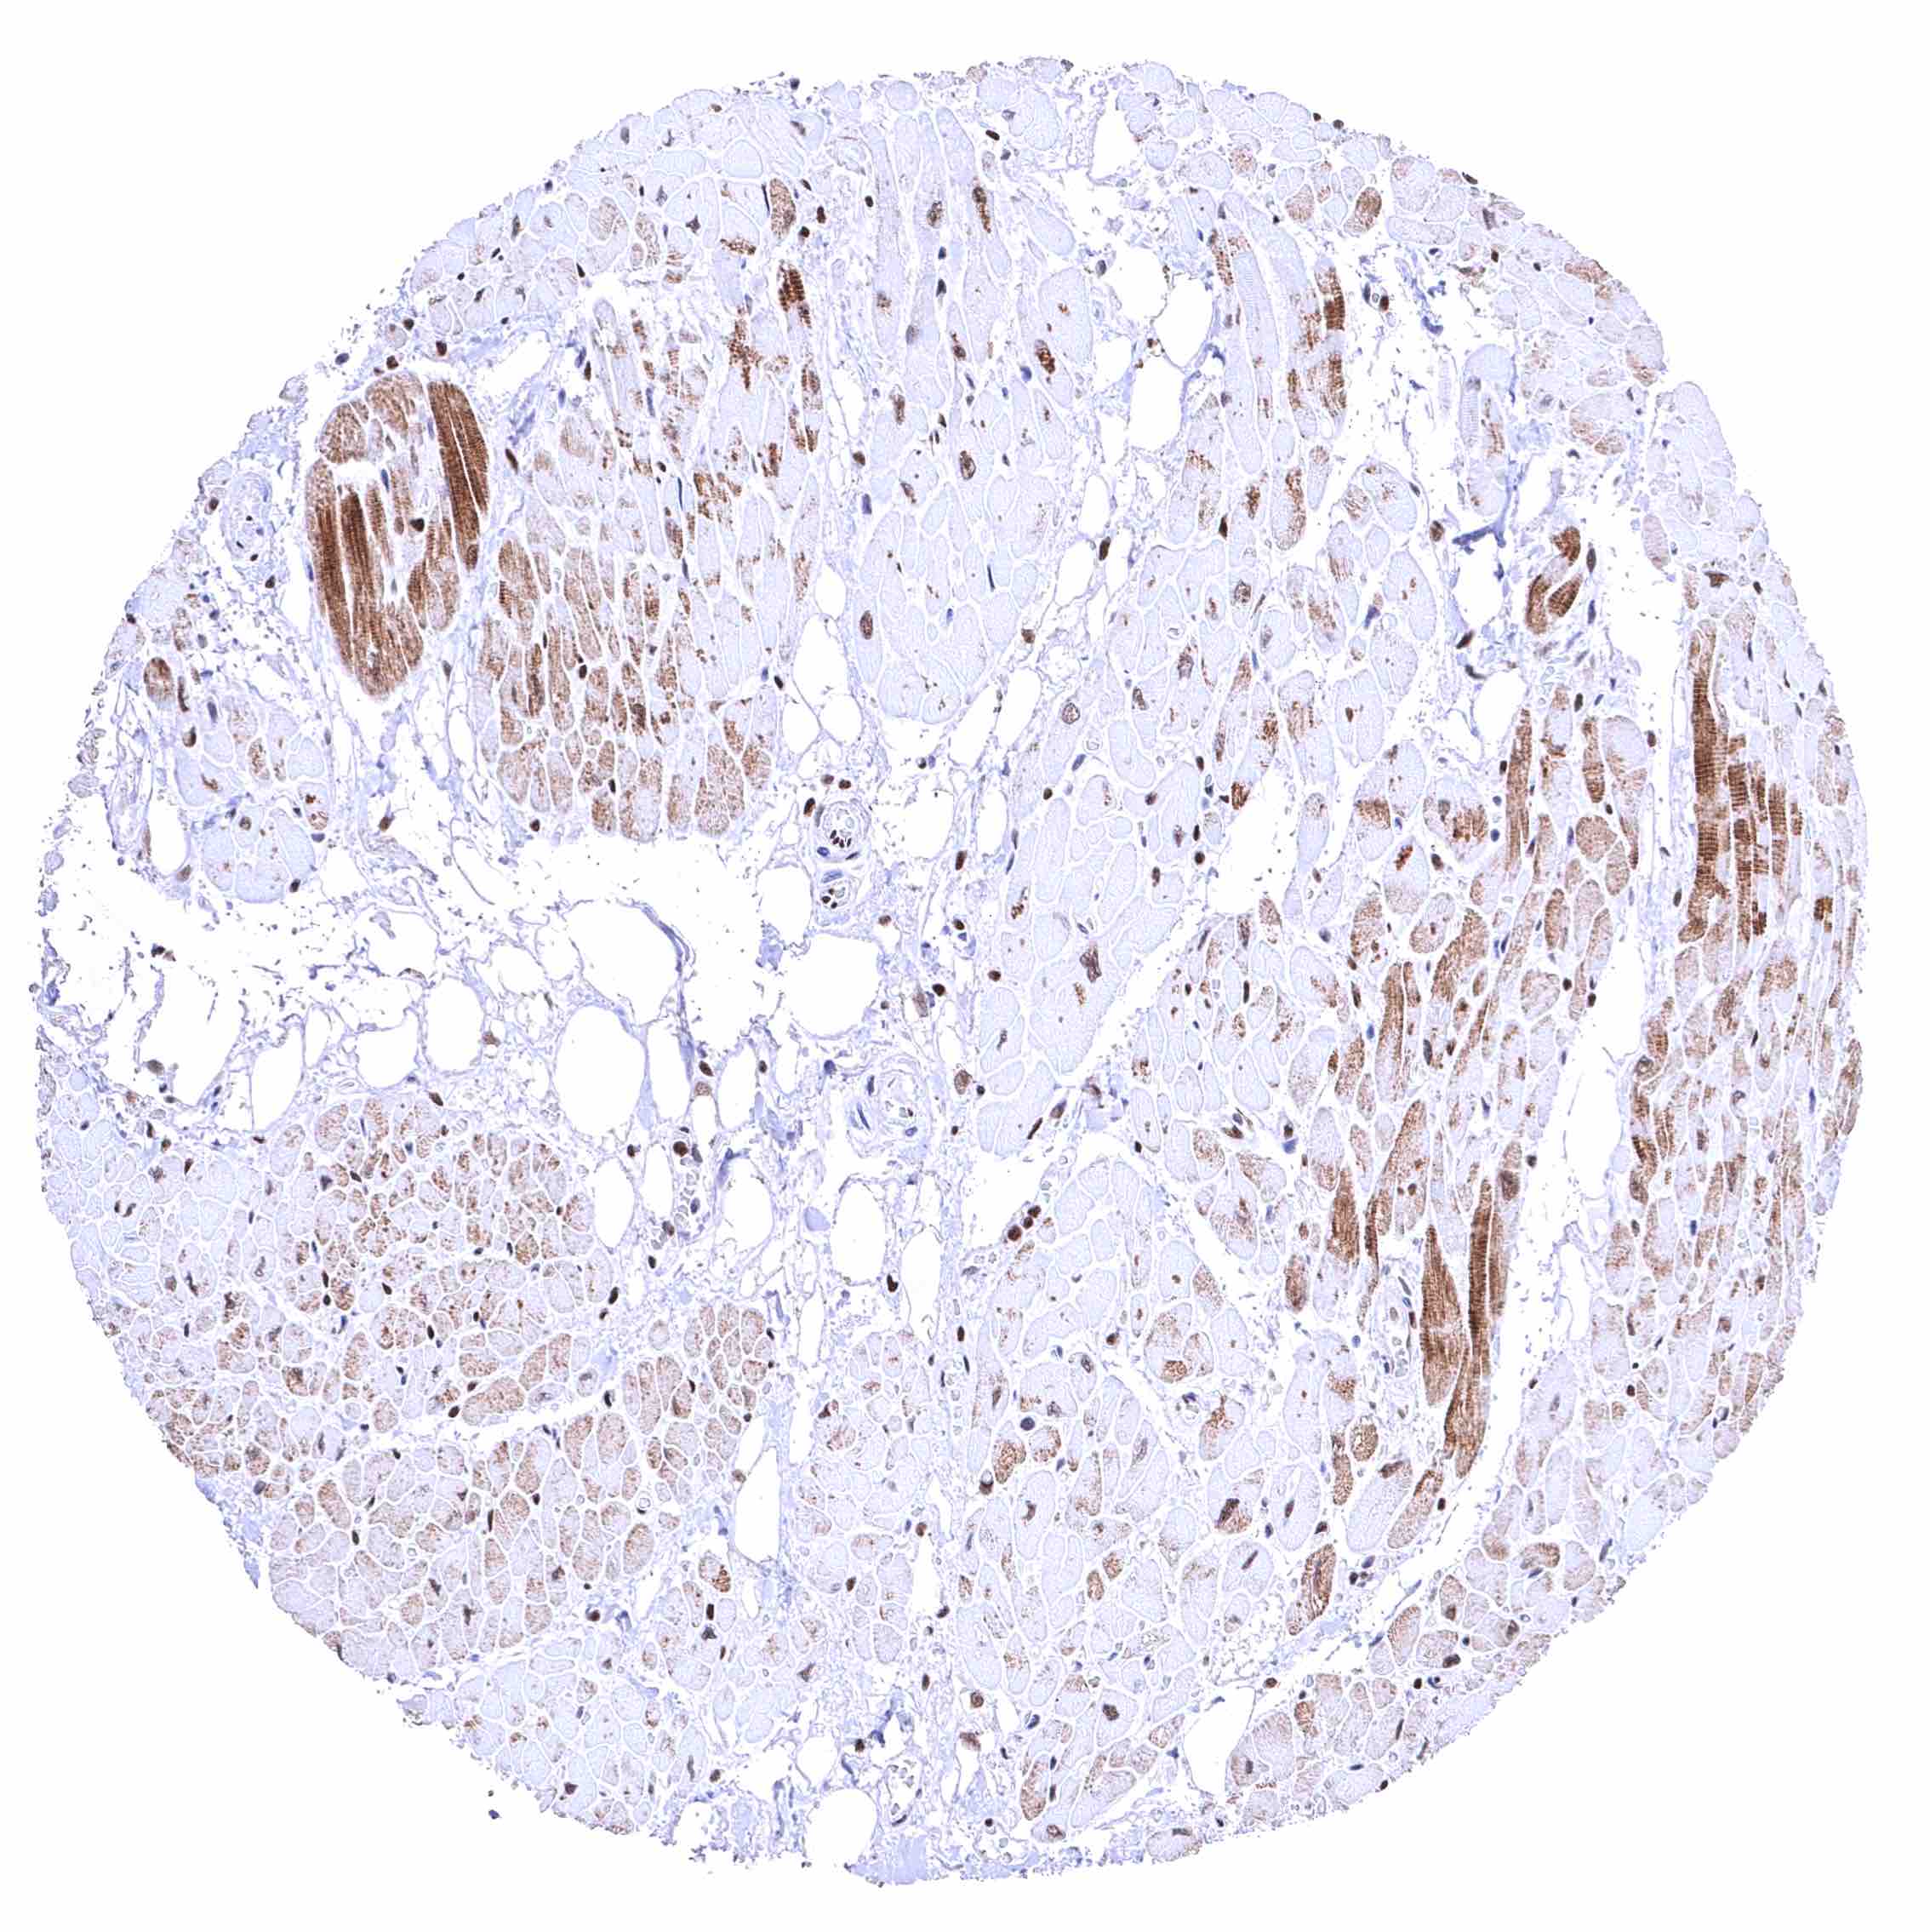

BRD4 antibody [HMV4275] HistoMAX™

Skeletal muscle – Distinct nuclear BRD4 staining of all cells. The additional cytoplasmic staining of some muscle cells may represent an antibody specific cross-reactivity.

Skeletal muscle – Distinct nuclear BRD4 staining of all cells. A cytoplasmic staining of muscle cells is not seen in this sample.